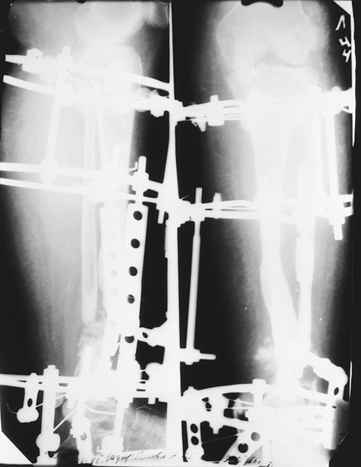

На втором этапе произведёно освежение краёв костных фрагментов б/б и м/б костей с приданием проксимальному фрагменту б/б кости впалой, а дистальному выпуклой формы, открытие канала проксимального фрагмента и погружной остеосинтез, а также остеотомия б/б кости в в/3 и м/б кости на границе с/3 и н/3 голени. Больной проводился одновременный бифокальный компрессионно-дистракционный остеосинтез. Достигнуто 11 см. удлинение и сращение ВПГ.

Срок лечения 11 месяцев. Наблюдение 2 года.